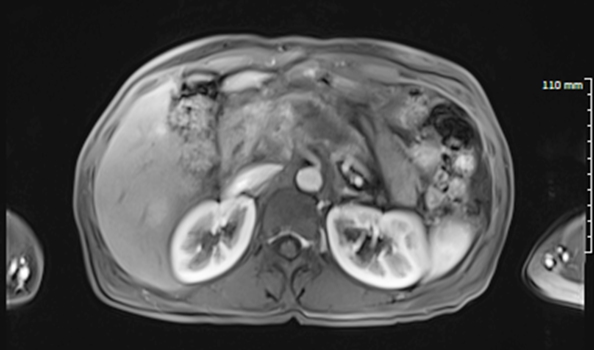

한편, 서울하이케어의원 김태희 원장은 50대 여자의 췌장암에서 간으로 전이된 환자 치료사례를 소개했다. 이 환자는 약 4.5cm 정도의 큰 췌장암이 있었고 간까지 전이됐다.

김태희 원장은 " 전이성 간암과 췌장 부위도 같이 치료했고,  ‘하이푸’ 시술 후 며칠이 지나자 전이성 간암으로 아팠던 우측 복부 통증도 사라지고 ‘췌장암’으로 인한 후복막 통증도 좋아져 누워서 잘 수 있게 됐다"고 설명했다.